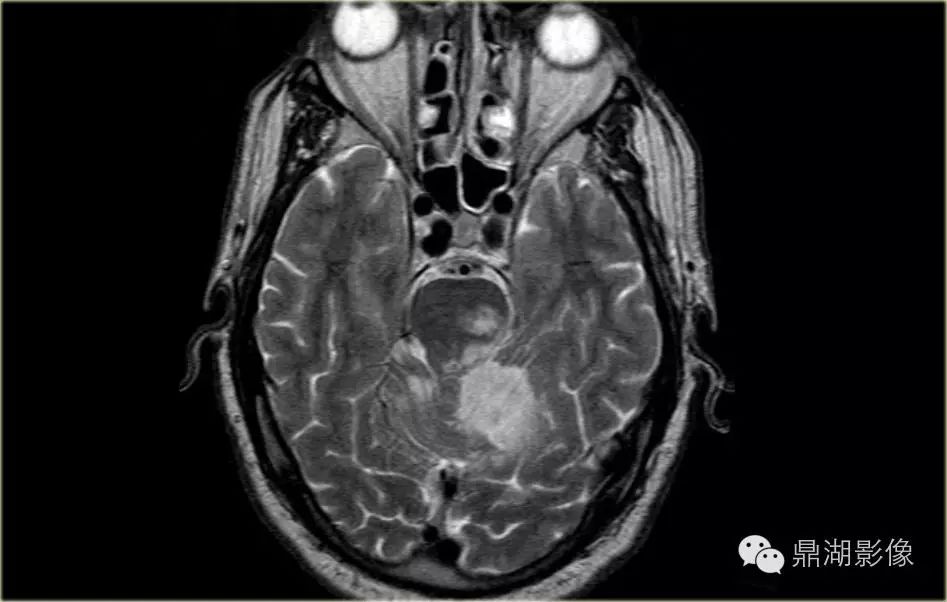

小脑后下动脉梗塞

049407cca69df20d05fdb709694f623a.gif